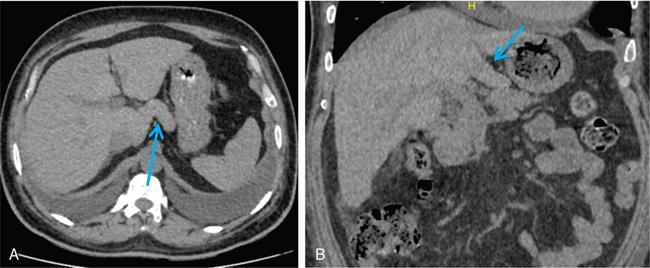

Ritu K. Kashikar, Shrinivas B. Desai Imaging is the mainstay of noninvasive diagnosis of the spectrum of abdominal pathologies or proving absence off thereof. Knowledge of normal anatomy and important normal variants is thus essential for the radiologist in order to avoid misinterpretation or erroneous diagnosis. This chapter highlights the normal anatomy of the hepatobiliary systems including the blood vessel and draining ducts and discusses relevant anatomical variants which may have important clinic implications. The liver is the largest abdominal organ, occupying the right upper abdominal quadrant and is in close approximation with the diaphragm, stomach and the gallbladder. It is largely covered by the costal cartilages. The liver is encapsulated by Glisson’s capsule which is a dense layer of connective tissue. It is covered by peritoneum, except in the regions of gallbladder fossa, fossa for inferior vena cava (IVC), and the bare area. The bare area is the posterocranial aspect of the liver, adjacent to the dorsal body wall, which is not covered by peritoneum. The liver has two surfaces, the convex diaphragmatic surface and a concave visceral surface. The slit in the hepatic hilum is called the porta hepatis and is penetrated by the right and left hepatic ducts (LHDs), hepatic artery and portal vein (PV). The distal portion of the lesser omentum is called the hepatoduodenal ligament and contains the common bile duct (CBD), hepatic artery, PV, nerves of liver and lymphatics. The liver has dual blood supply with hepatic artery providing 25% of hepatic blood and rest by portal vein (Fig. 9.2.1). Five ligaments connect the liver to the undersurface of the diaphragm. These include the falciform, the coronary and two lateral ligaments, all of which are peritoneal folds. The fifth ligament is a fibrous cord-like structure and represents the obliterated umbilical vein. The peritoneum invaginates into the liver parenchyma leading to formation of fissures. There are four normal fissures: fissures for the ligamentum teres, ligamentum venosum and gallbladder and the transverse fissure (Fig. 9.2.2). The liver is organized into microscopic functional units called lobules or acini. A central terminal hepatic venule surrounded by four to six terminal portal triads form a polygonal unit called the hepatic lobule. The terminal portal triad branches line the periphery of the unit. Between the terminal portal triads and the central hepatic venule the hepatocytes are arranged in one cell thick plates, surrounded by sinusoids. The blood flows from the terminal portal triad through sinusoids into terminal hepatic venule. Bile formed within the hepatocytes empties into terminal canaliculi which coalesce into the bile ducts (Fig. 9.2.3). This structure of the functional hepatic unit forms the basis of various functions of the liver. The normal relations of the liver are: The liver can be divided into right, left and caudate lobes. The right and left lobes are separated by the interlobular fissure and is oriented along a line passing through the gallbladder fossa inferiorly and the middle hepatic vein (MHV) superiorly (Fig. 9.2.4). This plane runs from the left of the IVC to the left of the gallbladder fossa and is a called the Cantlie’s line. Use of standardized, segmental anatomy is imperative because it facilitates communication and treatment planning. The segmental anatomy of liver is primarily based on vascular anatomy. The right lobe is divided into anterior and posterior sectors by of the right hepatic vein (RHV). The left lobe is divided into medial and lateraI sectors by an oblique plane connecting the left hepatic vein (LHV) and the falciform ligament. The liver is divided into upper and lower segments at the level of main portal vein (MPV) bifurcation (Fig. 9.2.5). Various systems are used in classification of liver anatomy. These are discussed in Table 9.2.1. The Couinaud’s system is the most commonly used and divides eight sections/segments which are discussed in details below (Table 9.2.2). 1. Segment 1 – Caudate lobe Bounded anteriorly and medially by the fissure for ligamentum venosum (Fig. 9.2.6). 2. Segment 2: Superior segment of the left lateral sector/section Bounded medially by falciform ligament and inferiorly by plane of MPV, also known as the posterior lateral sector (Bismuth, FCAT) (Fig. 9.2.7). 3. Segment 3: Inferior segment of left lateral sector/section Bounded medially by the falciform ligament and superiorly by the plane of the MPV bifurcation, also referred to as lateral anterior sector (Bismuth, FCAT) (Fig. 9.2.8). 4. Segment 4: Left medial sector/section Bounded laterally by falciform ligament and medially by Cantlie’s line (Fig. 9.2.9). 5. Segment 5: Inferior segment of the right anterior sector/section Bounded anteriorly by the gallbladder fossa and posteriorly by the plane of the RHV, superiorly bounded by the plane of MPV bifurcation (Fig. 9.2.10). 6. Segment 6: Inferior segment of the right posterior sector/section Bounded anteriorly by plane of the RHP and superiorly by the plane of the MPV bifurcation (Fig. 9.2.11). 7. Segment 7: Superior segment of the right posterior sector/section Bounded anteriorly by the plane of the RHV and inferiorly by the plane of the MPV bifurcation (Fig. 9.2.12). 8. Segment 8: Superior segment of the right anterior sector/section Bounded anteriorly by the plane of the gallbladder fossa and MHV, posteriorly bounded by the plane of the RHV and inferiorly by the plane of the MPV bifurcation (Fig. 9.2.13). Owing to its broad area of contact with the anterior abdominal wall, the liver is an ideal organ for evaluation with sonography. Ultrasound is commonly used for evaluation of size of the liver. On longitudinal scans obtained through the midhepatic line, if the liver measures 13 cm or less, it is normal in 93% of individuals (Fig. 9.2.14). The size of liver in various planes is discussed in chapter on normograms. When the area of contact between the liver and the anterior border of the right kidney, exceeds below two thirds of the kidney, the liver is considered as enlarged. The normal liver is homogeneous with fine echoes and appears evenly bright. The hepatic veins, PV and fissures interrupt the homogeneity of the liver parenchyma (Fig. 9.2.15). The parenchymal echogenicity may vary depending on the equipment, transducer and gain settings and should be judged by comparison with internal references like right renal cortex, body of the pancreas and PV walls. When compared with the adjacent normal right renal cortex the liver normally appears hyperechoic or isoechoic. The pancreas in a young individual is hypoechoic compared to the liver, and isoechoic in middle aged adults. As age progresses and fatty infiltration of the pancreas occurs, the pancreas appears hyperechoic to the liver. The liver is hypoechoic to the spleen. The normal liver reveals a density of 55–65 HU on nonenhanced scan and should appear homogenous with the exception of hypodensity in the regions of vessels and fissures. The liver parenchymal enhancement is minimal the arterial phase, with increase in density by only approximately 10 HU. This phase is usually to access vascular anatomy and to detect neovascular enhancing lesion like HCC, metastasis. Considering the fact that 75% of heptic venous supply is from the PV, the normal hepatic parenchyma shows maximum enhancement in the portal venous phase. During the venous/delayed phase the hepatic attenuation starts falling (Fig. 9.2.16). The hepatic fissures appear as linear fat containing structures. All the four fissures are well identifies on CT (Figs. 9.2.17–9.2.20). Normal liver should demonstrate uniform T1 signal similar or isointense to the paraspinal muscles and slightly hyper intense to the spleen. No signal drop should be seen on in or opposite phase. On T2W1 images liver appears slightly hyperintense to paraspinal muscles, isointense to pancreas and hypointense to spleen (Fig. 9.2.21). Following administration of extracellular contrast agents the normal liver parenchyma enhances on PV phase similar to that seen on CT. The arterial phase is preserved to determining vascular anatomy, variants and tumoural enhancement. Gadoxetic acid (Eovist) and gadobenate dimeglumine (MultiHance) are hepatobiliary agents showing excretion by the liver. In the case of gadoxetic acid, hepatic excretion is ~50%, which allows imaging in the hepatobiliary phase at ~20 minutes following injection. Gadobenate has only 3%–5% biliary excretion with hepatobiliary phase at approximately 40 minutes (Fig. 9.2.22). This property makes these agents useful in detection of nonhepatocyte containing lesions which appear hypointense to background liver on hepatobiliary phase. Hepatic anatomic variants are relatively common and represent normal interindividual variation of liver morphology. Normal Anatomic Variants Anatomic anomalies Accessory and pseudofissures may be seen in the liver. True accessory fissures result from infolding of the peritoneum usually along the undersurface of the liver and are rare. The inferior accessory fissure is the commonest accessory fissure and divides the posterior segment of the right hepatic lobe into lateral and medial portions. Diaphragmatic slips may cause indentation over the liver surface and are not commonly seen on imaging (Fig. 9.2.23). Leftward extension of the lateral segment of the left hepatic lobe appearing as a crescentic density that wraps around the spleen is referred to as sliver of liver. The left lobe of the liver may exhibit various forms: leaf like; spatular; truncated pyramid/wedge shaped; and a bifid appearance (Fig. 9.2.24). Elongated left lobe may be mimic splenomegaly, perisplenic hypoechoic collections or less commonly tumours. Imaging clues to diagnosis are establishing contiguity with liver and visualization of parenchymal vessels coursing through. The portion of the liver that extends medially from the right lobe between the IVC and fissure for ligamentum venosum is called the caudate lobe. The caudate lobe is divided inferiorly into a lateral caudate process and a medial papillary process. The medial papillary process projects medially towards the pancreatic head and has applied importance (Fig. 9.2.25). Riedel’s lobe is a tongue-like projection from the anterior aspect of the right lobe and the most common accessory lobe of the liver. It is seen most frequently in asthenic women. The reported prevalence of RL, ranges from 3.3% to 14.5% and the prevalence is higher in women than in men. It can be 20 cm or more in length and may extend up to the iliac fossa. It is usually asymptomatic and is discovered incidentally (Fig. 9.2.26). Accessory liver lobes are defined as a supernumerary lobe of normal hepatic parenchyma in continuity with the liver. This is a rare entity and usually occurs as a result of congenital ectopic hepatic tissue, although rarely may occur as a result of trauma or surgery. Various systems are proposed for classification of ALL. Another method of classification has been proposed based on biliary drainage and presence or absence of capsule. Accessory lobes can be readily diagnosed and characterized on CT or magnetic resonance imaging (MRI) done for related or unrelated conditions. CT shows the lesion as a soft–tissue density mass attached to the liver and isodense to the organ. The portal/hepatic venous branches can be seen coursing through it, in contiguity with the liver (Fig. 9.2.27). The coeliac axis trifurcates into common hepatic, splenic and left gastric arteries at the level of T12–L1. The common hepatic artery becomes the proper hepatic artery after origin of the gastro-duodenal artery. The hepatic artery proper ascends anterior to the PV and medial to the CBD and divides in to right and left hepatic artery (LHA). Occasionally the middle hepatic (segment 4) artery arises from hepatic artery proper. The hepatic artery appears as a tubular hypoechoic structure and shows antegrade flow on Doppler (Fig. 9.2.28). Normally the resistive index is low ranging between 0.55 and 0.7. The hepatic artery, its anatomy, branches, course, calibre are best evaluated on arterial phase of dynamic CT (Fig. 9.2.29). This is also the preferred modality prior to hepatobiliary surgical planning. Contrast-enhanced MRI also shows the above details but spatial resolution is lower. Road map of the arterial vascularity of the donor and recipient is a prerequisite for transplant surgery and complex hepatobiliary surgery. Detailed hepatic arterial anatomy and its variations have its significance in liver surgeries and interventional hepatic procedures, relative to the hepatic lobe involved. A classification method was described by Michel et al. in 1955, and is discussed in Table 9.2.3 (Fig. 9.2.30). I: standard anatomy ~60% (range 55%–61%) II: replaced LHA ∼7.5% (range 3%–10%) III: replaced RHA ~10% (range 8%–11 %) IV: replaced RHA and LHA ~1% V: accessory LHA from LGA ~10% (range 8%–11%) VI: accessory RHA from SMA ~5% (range 1.5%–7%) VII: accessory RHA and LHA ~1% VIII: accessory RHA and LHA and replaced LHA or RHA ~2.5% IX: CHA replaced to SMA ~3% (range 2%–4.5%) X: CHA replaced to LGA ~0.5% Other unclassified variants are: The two most common variants are the replaced right hepatic artery (RHA) arising from the SMA (Fig. 9.2.31) and replaced LHA arising from the left gastric artery (Figs. 9.2.32–9.2.34). Segment 4 artery – Middle hepatic artery (MHA) The middle hepatic artery usually arises from the LHA, it may, however, arise from the RHA (Fig. 9.2.35). The knowledge regarding origin of MHA is imperative in transplant surgery. The MHA can arise from RHA in Patients with replaced LHA. In patients with replaced RHA, the MHA arises from LHA (Fig. 9.2.36). Because of the considerable variability of hepatic arterial anatomy, assessment of this anatomy is crucial in the preoperative evaluation of potential living liver donors. Relevance of donor and recipient arterial anatomy is discussed in details in chapter on liver transplant. The relationship between the arterial variant and tumour is important to establish prior to major surgeries. Injuries to aberrant hepatic vessels and secondary ischaemic biliary strictures can be avoided. A replaced RHA has a more posterior course and long length. This variant may be advantageous in patients undergoing right lobar resection. However, there is greater propensity of involvement of replaced RHA by pancreatic head. The radiologist must be vigilant in reporting this variant (Fig. 9.2.37). Accessory RHA can, however, be sacrificed even if encased by neoplasm. An accessory LHA needs to be ligated separately in surgeries where blood supply in the porta hepatis is occluded. Replaced LHA from LGA maybe injured in case of surgeries at the level of hiatus. Hence this variant should be informed to surgeon in patients undergoing gastric surgeries. Preoperative mapping of the hepatic arterial anatomy prior to placement of intraarterial chemotherapy pumps is essential because it helps in deciding whether the candidate is suitable for the procedure and also if technical modifications are needed. The intraarterial infusion pump should be placed in the dominant hepatic artery as proximal as possible, but beyond GDA origin. Inpatients with standard anatomy, the pump is usually placed in the hepatic artery prior just after GDA origin. The location of pump can be modified in patients with variant anatomy, based on origin of GDA and dominant hepatic vessel. The PV is the main vessel in the portal venous system and drains blood from the gastrointestinal tract and spleen to the liver.